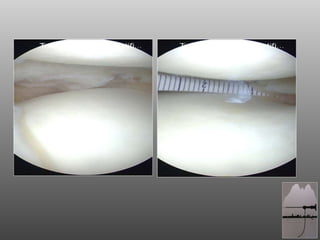

DOPO 1aa

CONCLUSIONI SALVIAMO IL MENISCO !! LO SCAFFOLD MENISCALE E’ LA MIGLIORE RISPOSTA AL GINOCCHIO PARZIALMENTE MENISCECTOMIZZATO ACCURATA SELEZIONE DEL PAZIENTE E CORRETTA TECNICA CHIRURGICA SERVONO F.U. PIU’ LUNGHI  RIGENERAZIONE DEL MENISCO CON FATTORI DI CRESCITA

CONCLUSIONI SALVIAMO ILMENISCO !! LO SCAFFOLD MENISCALE E’ LA MIGLIORE RISPOSTA AL GINOCCHIO PARZIALMENTE MENISCECTOMIZZATO ACCURATA SELEZIONE DEL PAZIENTE E CORRETTA TECNICA CHIRURGICA SERVONO F.U. PIU’ LUNGHI RIGENERAZIONE DEL MENISCO CON FATTORI DI CRESCITA